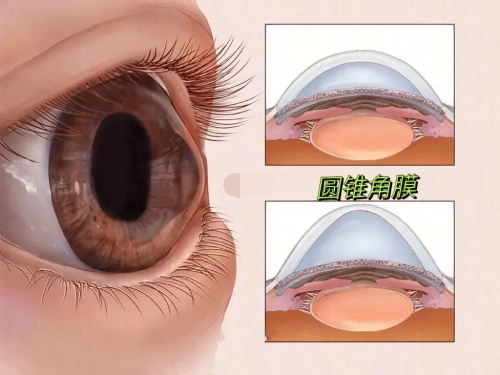

在高度近视并发症治疗方面,孙医生采用个性化方案,针对黄斑裂孔、视网膜劈裂等病变开展精密手术干预。

高度近视黄斑裂孔闭合率89%